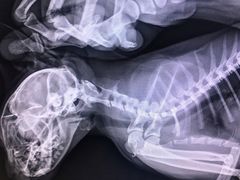

• 北京恒爱动物医院(清景园分院)

• -北京恒爱动物医院(清景园分院)